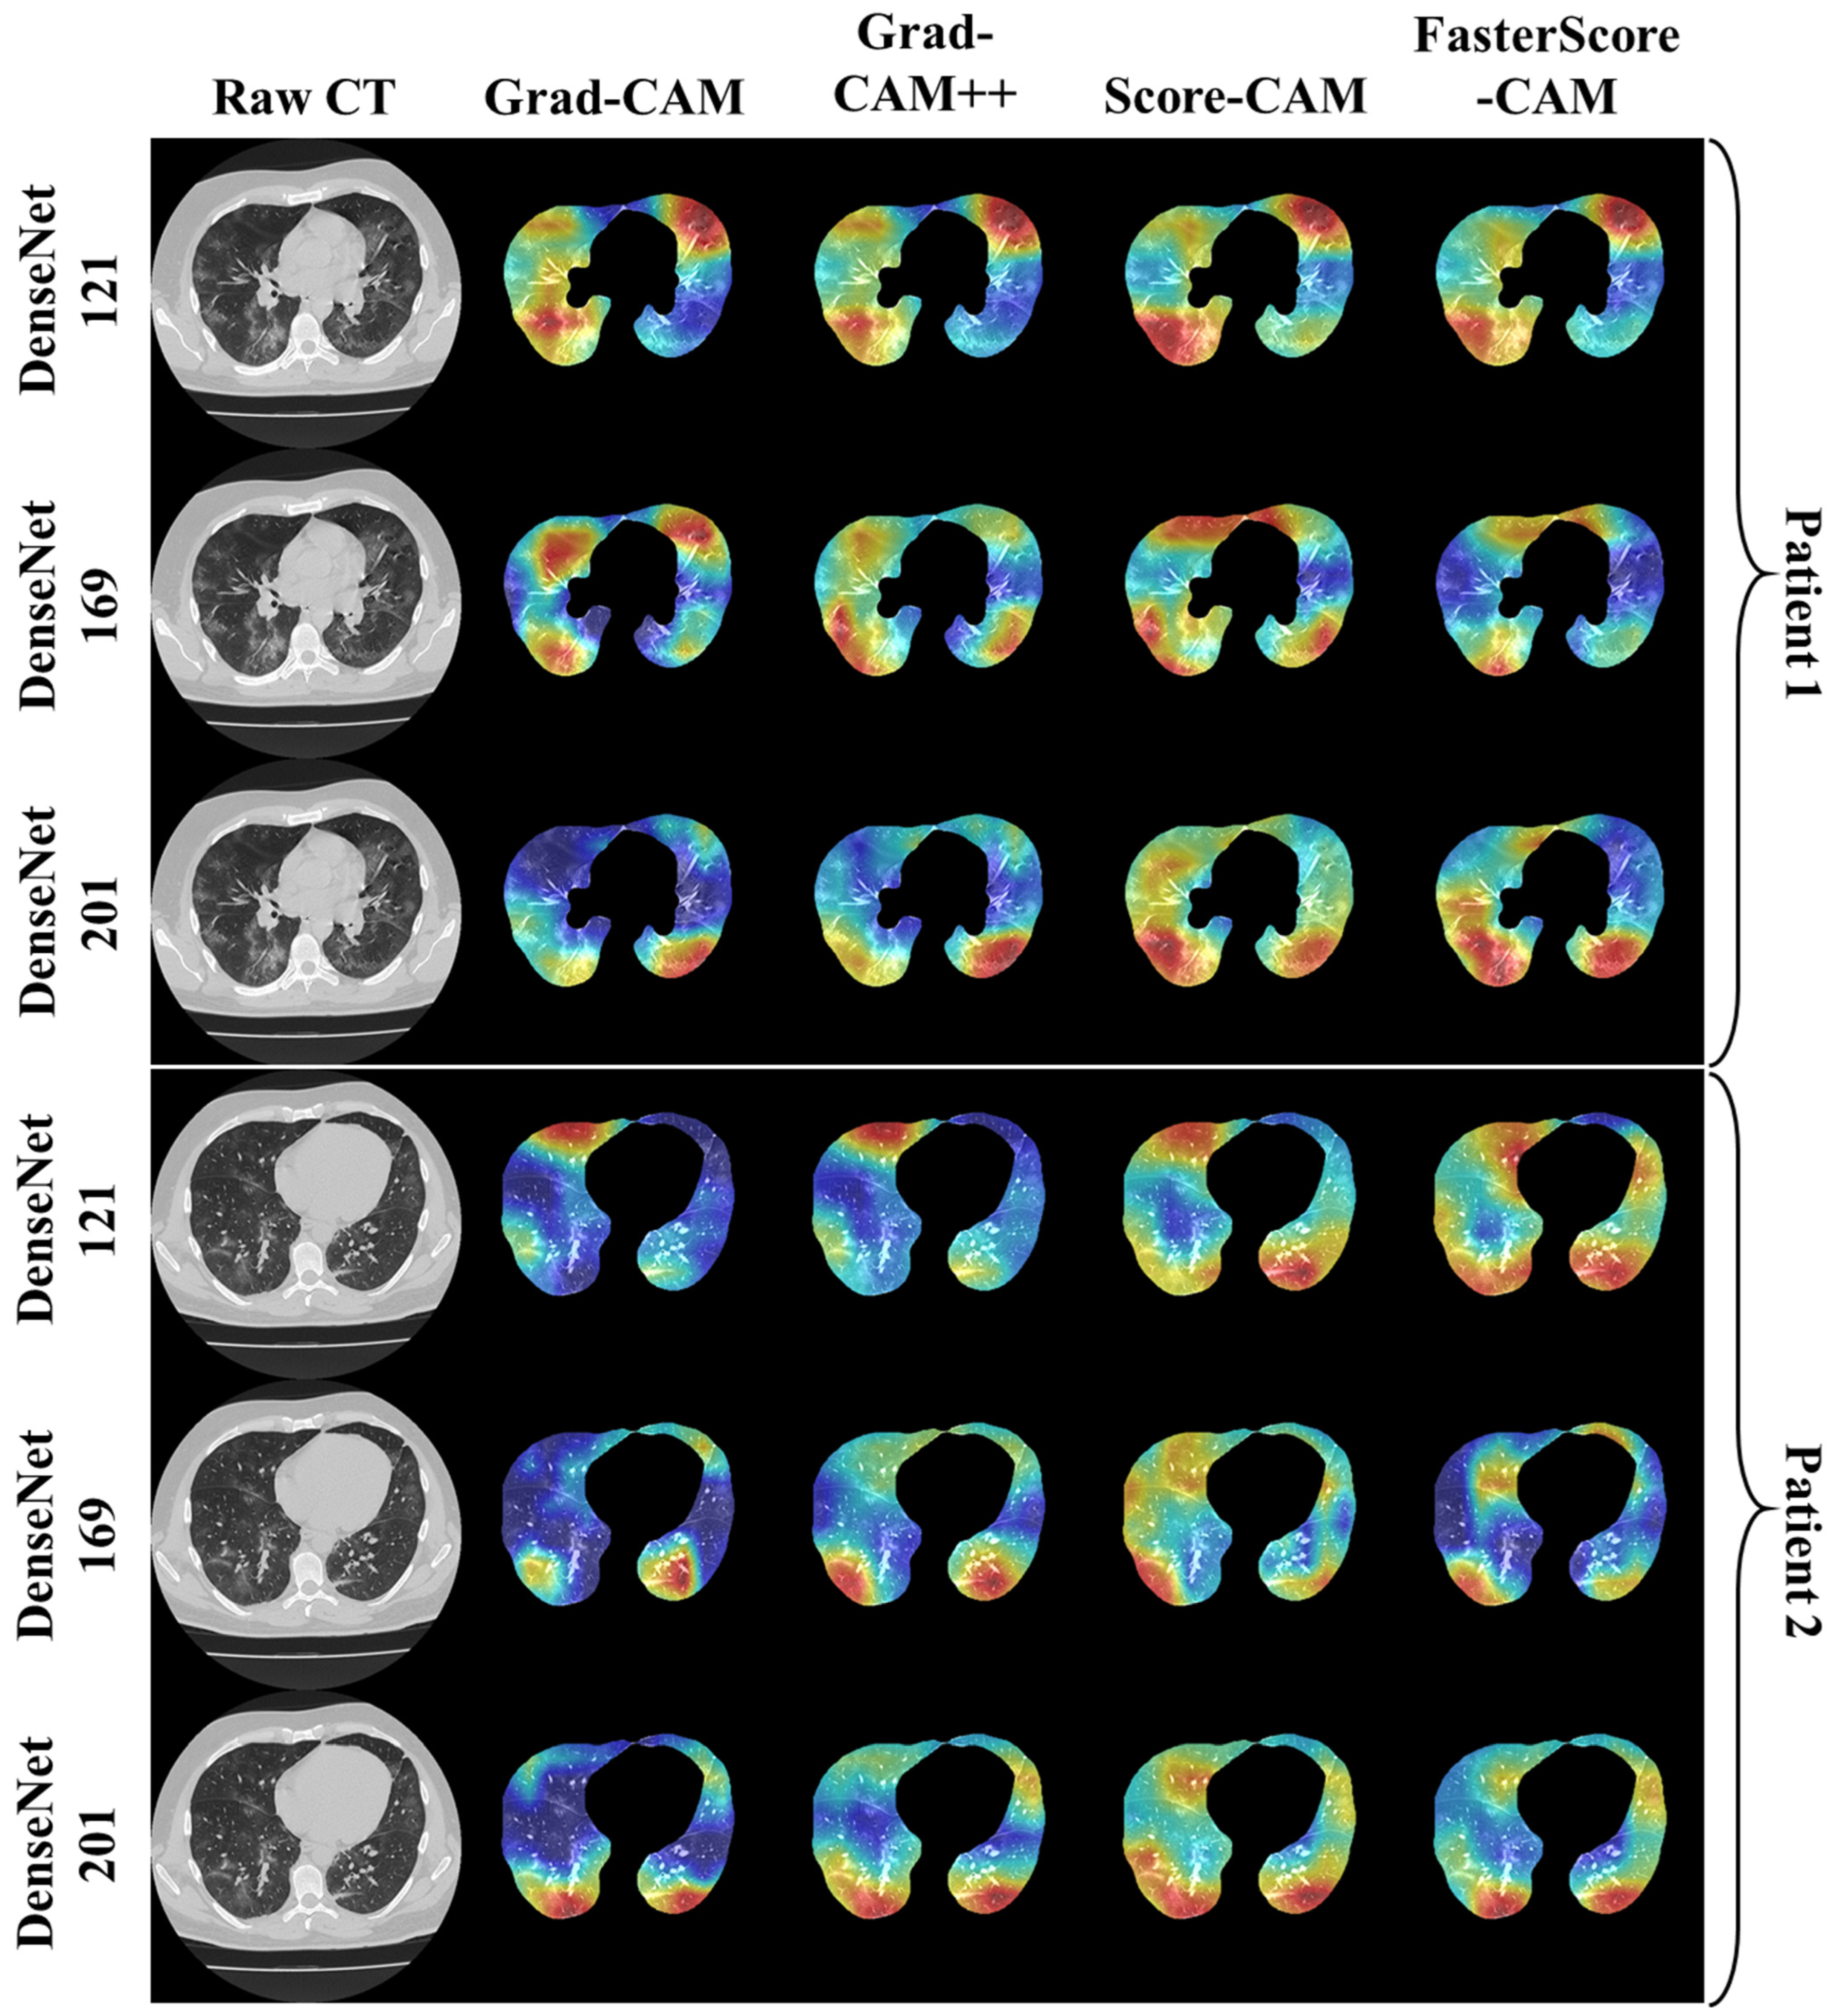

Visual Results Representing Lesion Using the Four CAM Techniques

4.1. Study Findings

4.4. A Special Note on Four CAM Models